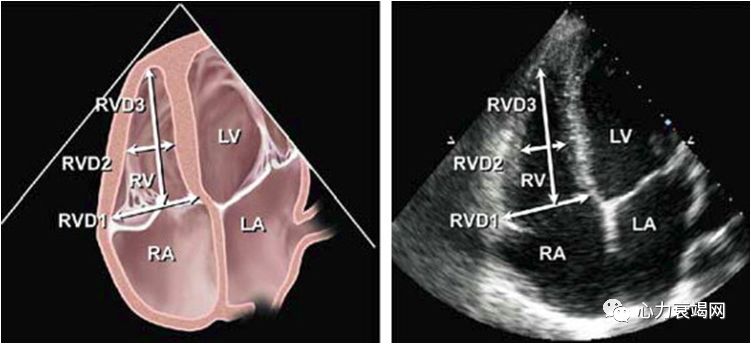

RVD1 > 42 mm;RVD2 > 35 mm;RVD3 > 86 mm。